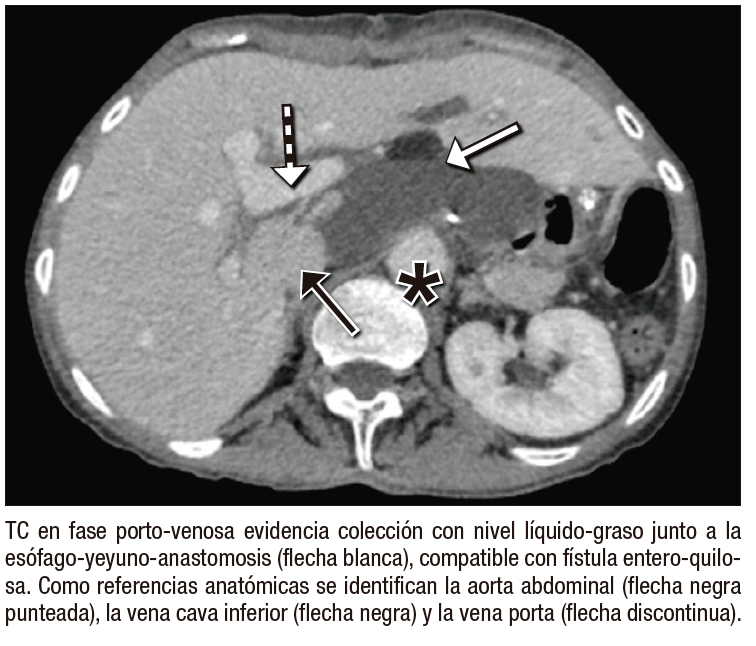

●Caso 2. Mujer de 57 años con antecedente de adenocarcinoma gástrico tratado mediante gastrectomía total y linfadenectomía. Posteriormente, presentó episodios de diarrea persistente, motivo por el cual se solicitó una TC de abdomen y pelvis con contraste endovenoso. El estudio demostró una colección con nivel líquido-graso en relación con la esófago-yeyuno-anastomosis, hallazgo característico de fístula entero-quilosa secundaria a lesión linfática. La paciente fue manejada de manera conservadora mediante punción percutánea evacuadora y régimen dietario, con evolución favorable.

Entre las complicaciones tempranas, la filtración anastomótica es una de las más graves, con incidencia reportada del 1% – 10% y elevada mortalidad.5 La TC es más sensible que el tránsito baritado para detectar colecciones con gas y extravasación de contraste.6, 7 La hemorragia posoperatoria, aunque infrecuente (0,5% – 5%), constituye una emergencia vital; la TC permite detectar hematomas y extravasación activa en fase arterial.8 La fístula entero-quilosa es poco común y secundaria a lesión linfática durante la linfadenectomía; en TC puede manifestarse como líquido hipodenso o colecciones con nivel líquido-graso.9 La pancreatitis aguda posoperatoria, generalmente relacionada con manipulación quirúrgica o compromiso vascular, puede confirmarse con TC mediante la identificación de necrosis focal y cambios inflamatorios.10 Finalmente, el infarto omental se observa como una masa grasa heterogénea con estriación del tejido adiposo, simulando absceso o recurrencia tumoral.11